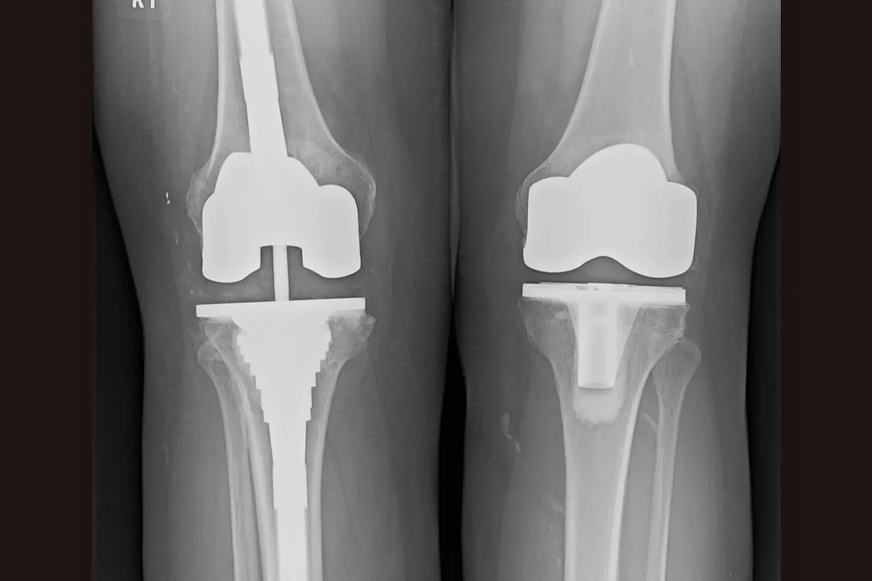

Revision knee replacement surgery is often considered when the implant starts to wear off, and your knee starts to pain again. The damaged implant is being replaced with the new one. Also, the damaged joint parts are repaired with specialised components. These procedures restore stability, relieve pain, and improve joint function.

Revision knee replacement is a complex procedure that is carried out to replace one or more components of the previously placed knee implant. Only those parts are removed and replaced that are worn out or damaged. Our specialists are highly experienced to carry out all types of revision surgeries, ranging from single worn or loose components to advanced implant damage involving all the components—femoral, tibial, and patellar.

The following are the techniques used for revision knee replacement, depending on patient needs and type of damage: